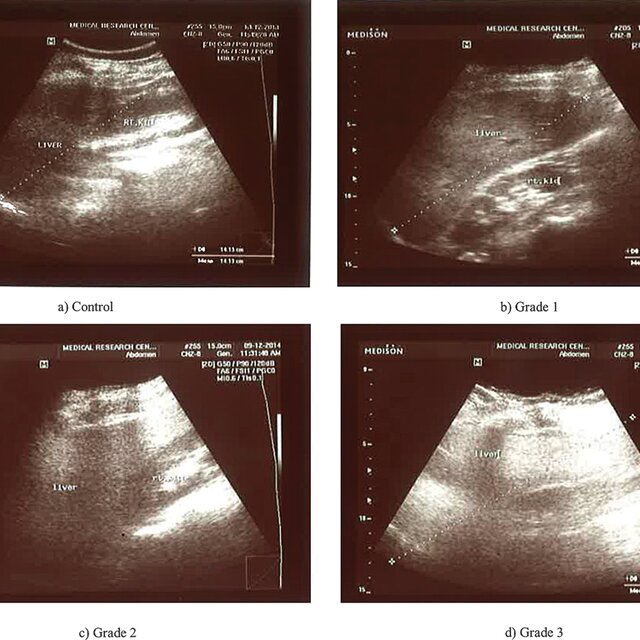

Grades of fatty liver on visual analysis. Ultrasound image shows (a …

Practice of Ultrasound: Part 13 — Liver fat and fibrosis

Qualitative assessment of liver fat with conventional ultrasound. (A …

Practice of Ultrasound: Part 13 — Liver fat and fibrosis